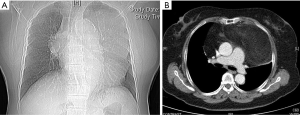

A 68-year-old woman was admitted to our department on September 20, 2019, with complaints of chest tightness and shortness of breath for more than 2 years, with chest tightness and shortness of breath being worse than before. The right upper limb and lower back were also in pain, but the patient was in good mental health. The patient had no history of fever, cough, hemoptysis, significant weight loss, or other symptoms. This patient has a 20 years of history of hypertension with blood pressure up to 180/110 mmHg, but her blood pressure was already under control. Other past medical history includes obsessive-compulsive disorder and cerebral infarction for 15 years. The patient’s personal and family medical history was unremarkable. The physical examination showed the trachea being slightly to the right, no chest deformity, normal respiratory motility, solid sound on percussion of left lung, and clear lung breathing at the auscultation of the right lung field. Her laboratory findings showed no significant abnormality. The chest X-ray result demonstrated a giant mediastinal tumor (Figure 1A). An enhanced chest computed tomography (CT) scan revealed a large mass of 20 cm × 10 cm × 8 cm in size in the anterior mediastinum, invading the pericardium and extending into the bilateral thoracic cavity and causing a mediastinal shift and lung collapse. Most of the mass showed fat density on the CT scan, the CT value was about −56 HU, and the anterior part of the mass was solid while the CT value was about 20 HU. A small amount of liquid was seen in the pericardial cavity, as shown in the figure (Figure 1B). The chest radiology specialists believed that the mass shown in the CT scan might be a mediastinal liposarcoma.

Therefore, surgical resection was performed on September 28, 2019. Median sternotomy was chosen to allow complete access to the bilateral thoracic cavity for a large tumor resection with the patient under general anesthesia (Figure 2A). The tumor was located in the anterior mediastinum with most part of it being in the left thoracic cavity, partially invading the pericardium and superior vena cava. During the operation, part of the pericardium was resected, and then part of the innominate vein was also resected with a vascular staple, and finally the tumors were completely separated and dissected (Figure 2B). The operation time was 98 min, the intraoperative blood loss was about 700 mL, and no blood transfusion was performed. The patient was transferred to the ICU with tracheal intubation.